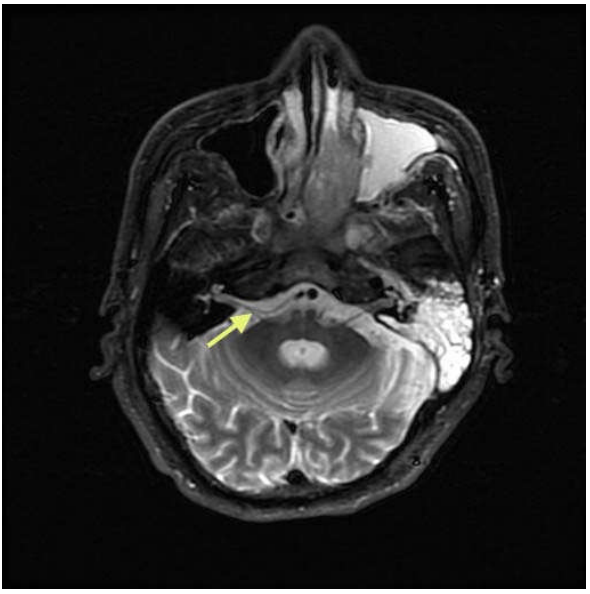

47.頭部MRI影像如下圖,箭號所指最可能是下列那一條顱神經?

(A)三叉神經(trigeminal nerve) (B)動眼神經(oculomotor nerve) (C)聽神經(acoustic nerve) (D)迷 走神經(vagal nerve)